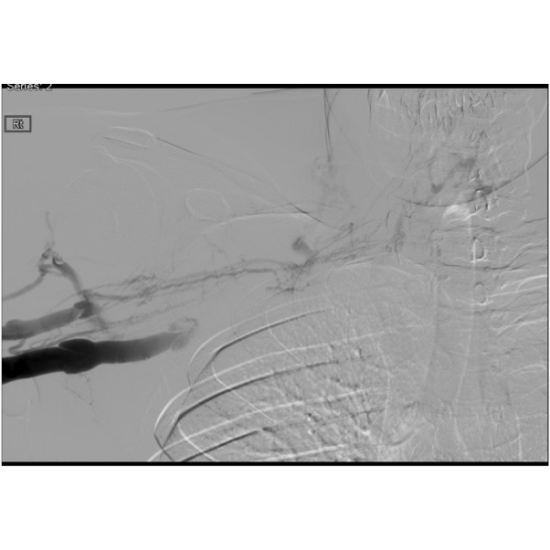

| Silent Killer - Page #3 | |||